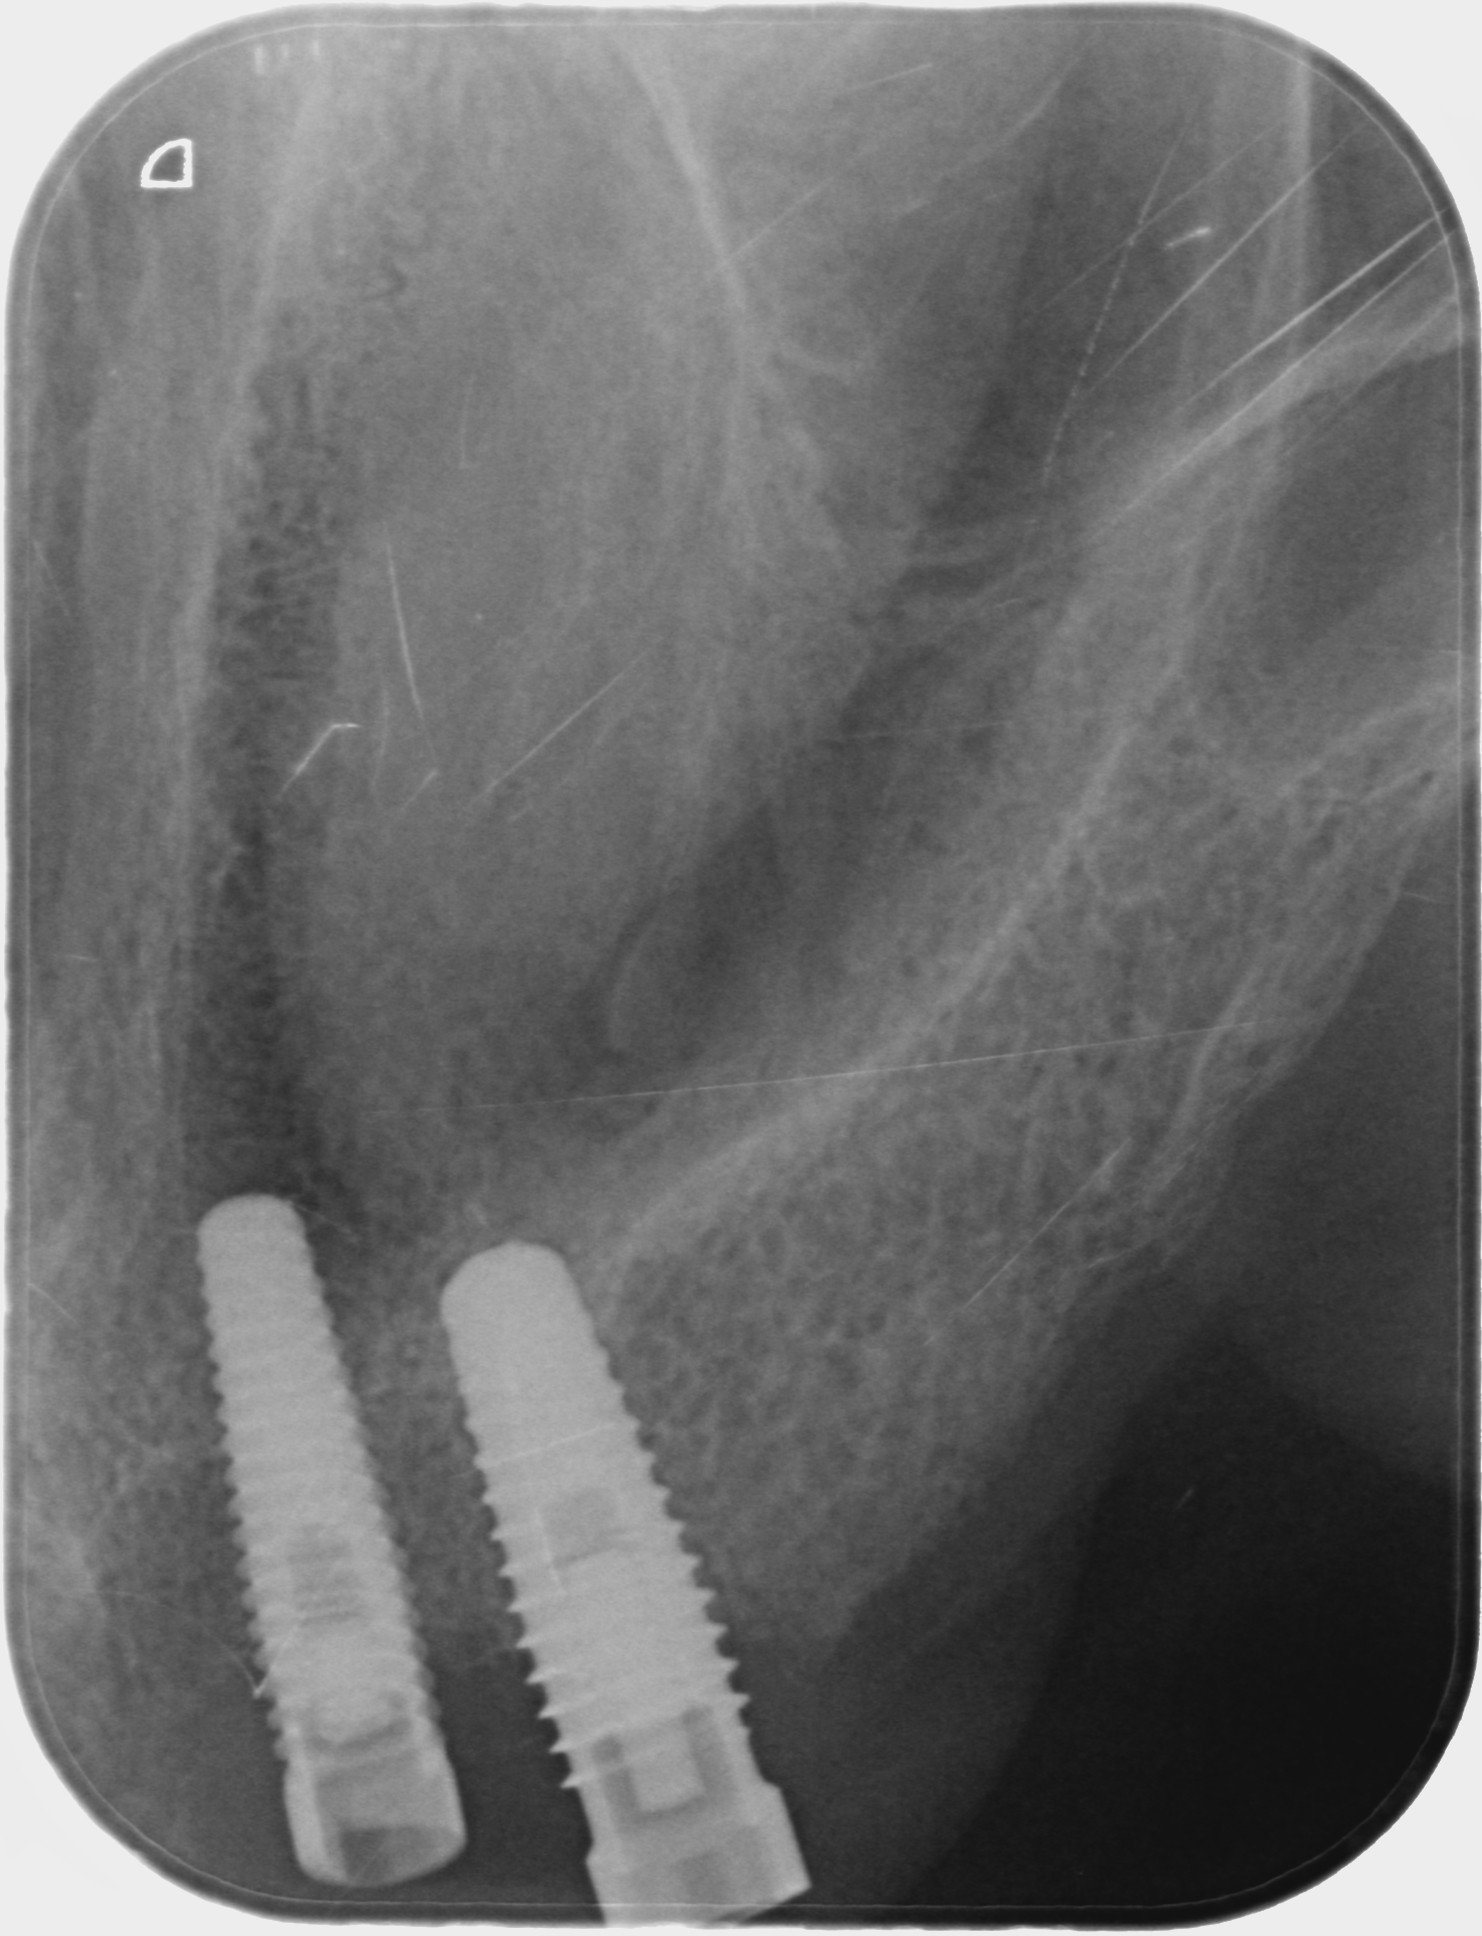

Buenas tardes, El caso que presento es una paciente quien acude a la consulta y presenta implantes colocados en otra clínica desde hacen 3 años. Las rx periapicales muestran un [...]